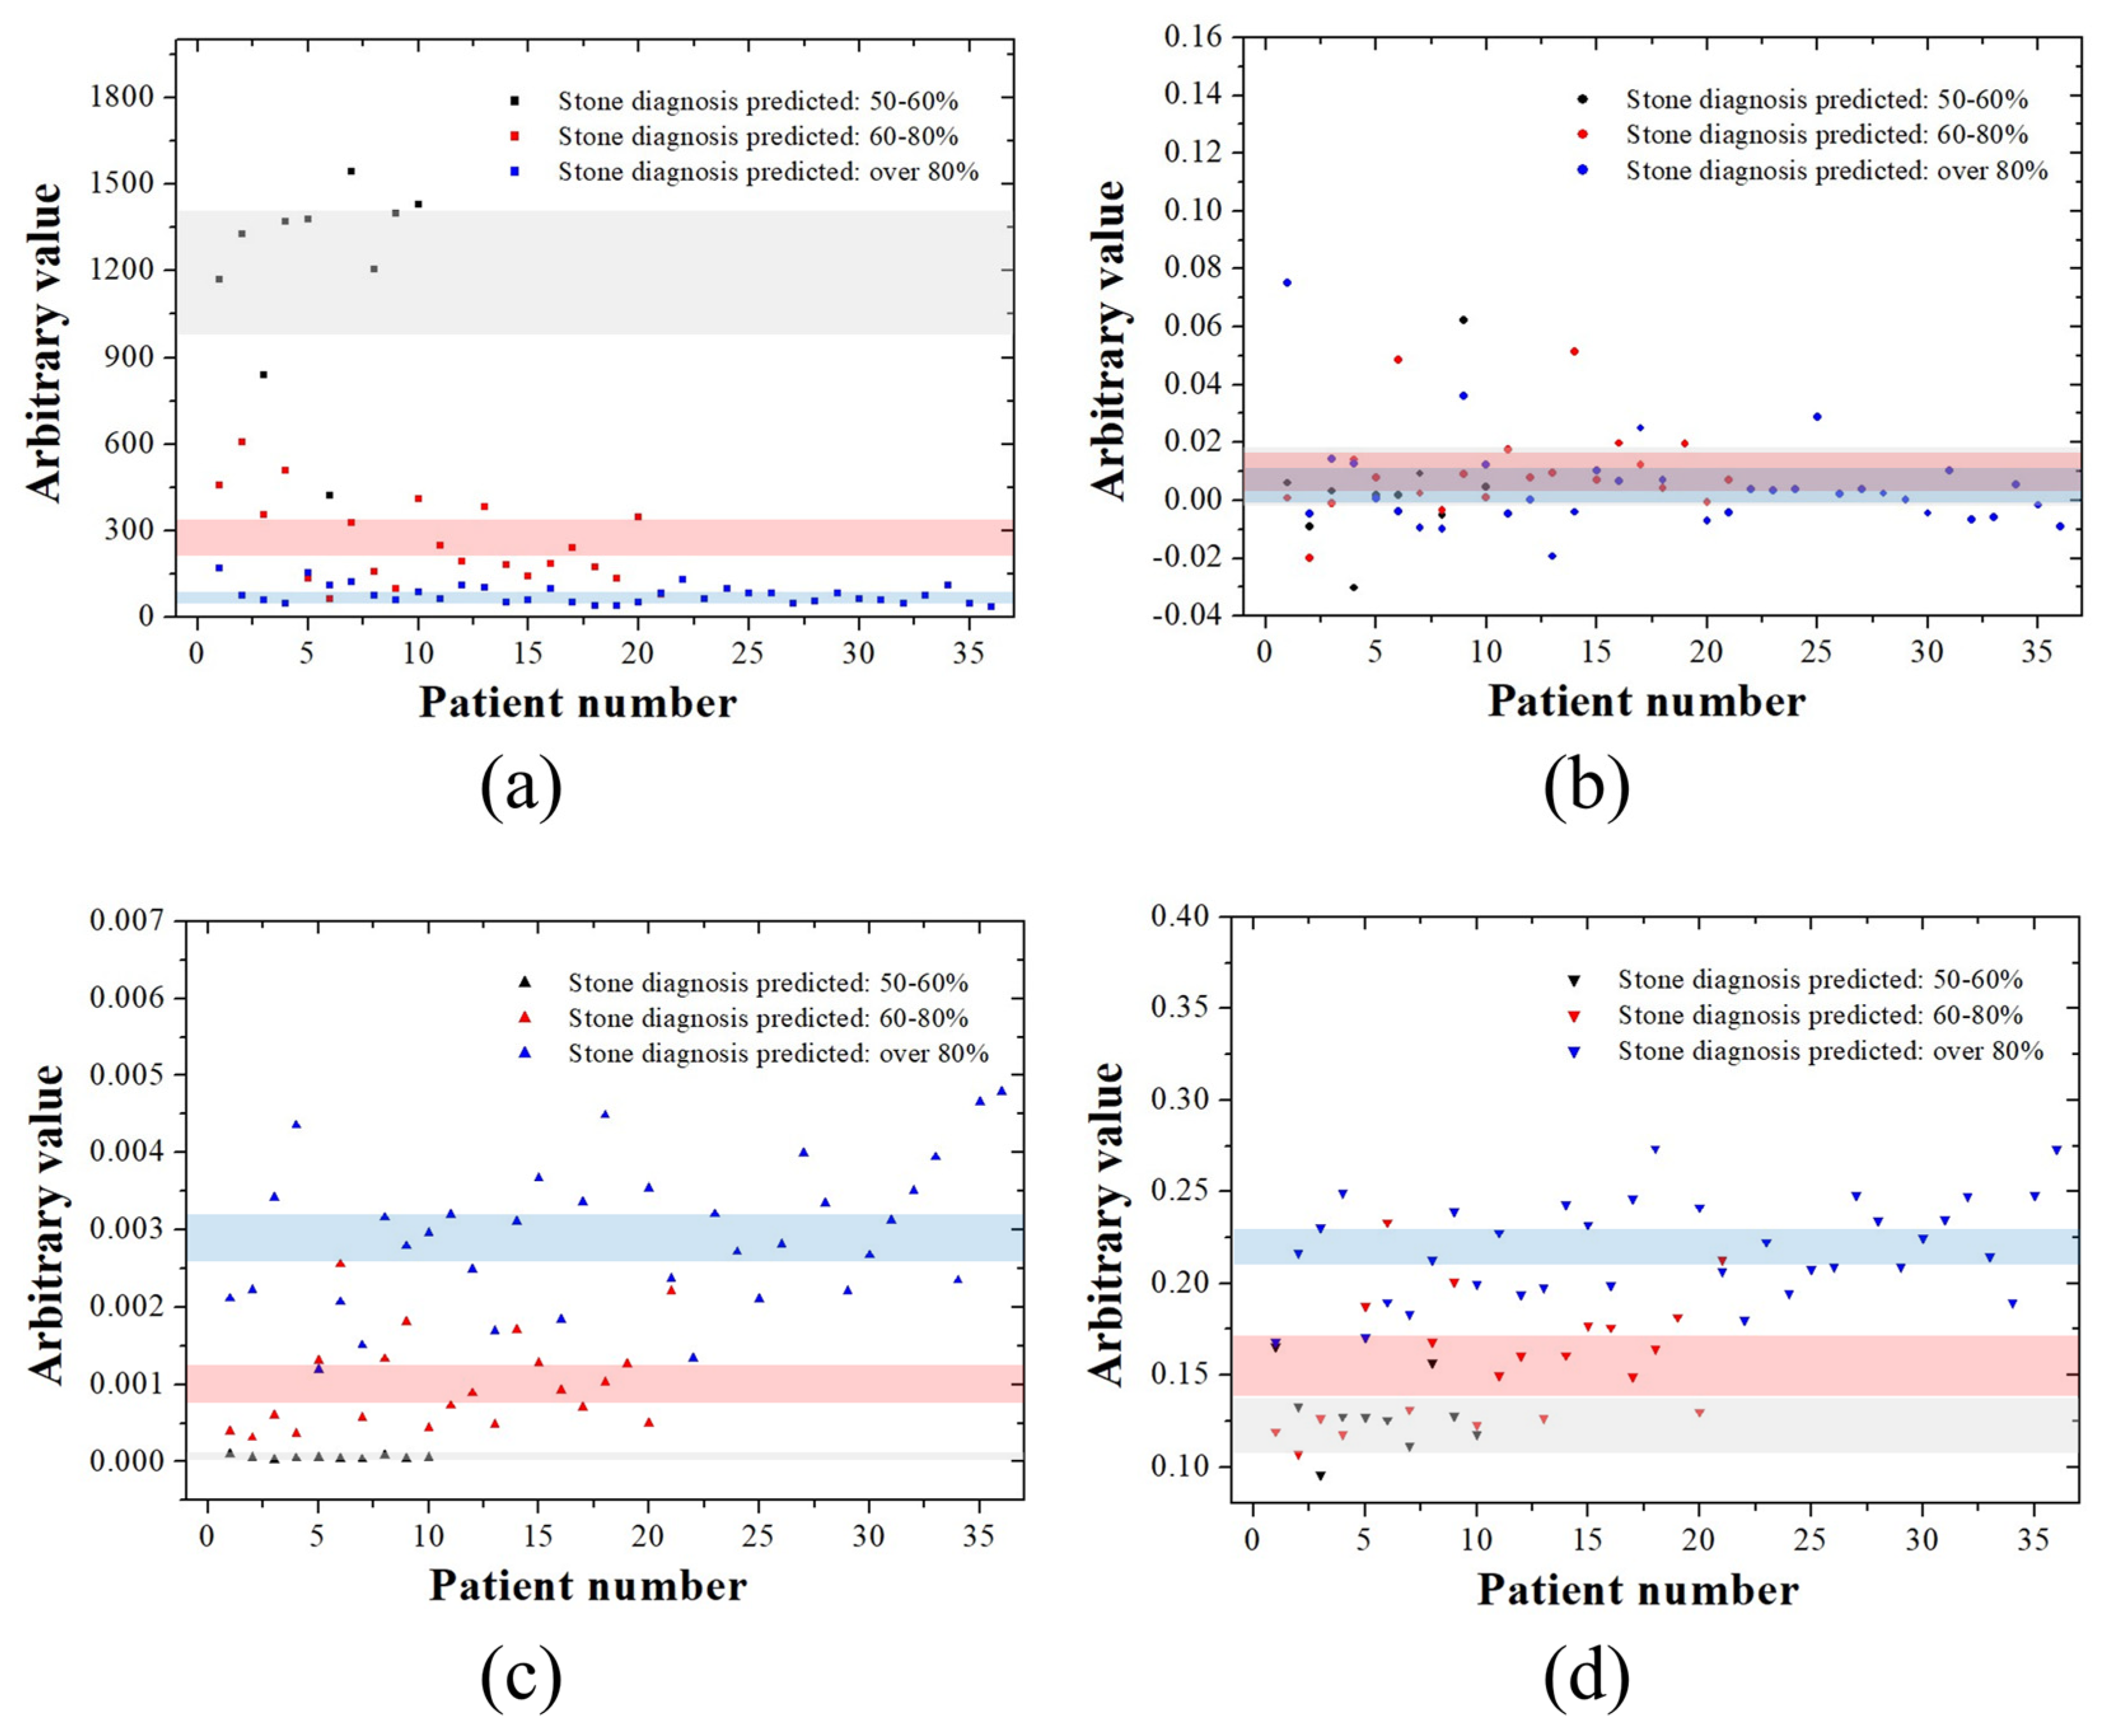

3. Results

| Disease Type | Expected Probability of Diagnosis | ||

|---|---|---|---|

| Number of Images with 50–60% Probability | Number of Images with 60–80% Probability | Number of Images with ≥80% Probability | |

| Kidney stone | 14 | 23 | 15 |

| Gallbladder stone | 10 | 21 | 35 |